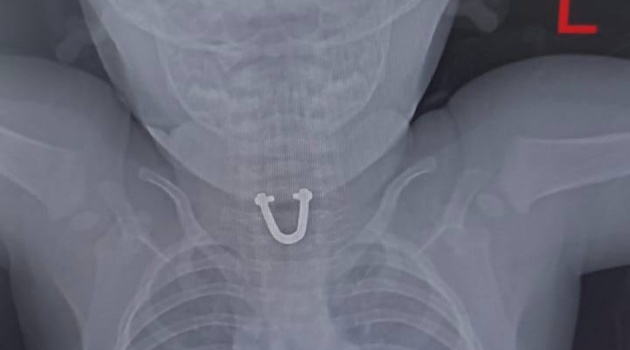

В Новороссийске врачи достали из пищевода малыша деталь от сумки